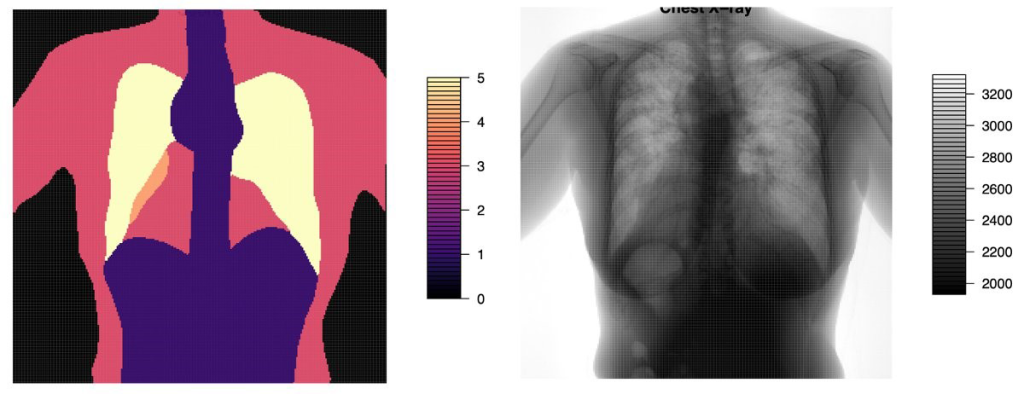

Fig. 1: An example of the Invicro chest X-ray intensity image and corresponding quality map.

To evaluate this approach, Invicro started with the Koniq10K natural image quality dataset, which has over 10,000 images at a resolution of 512*384 pixels. Each image has at least nine quality ratings from human viewers. They also developed an in-house chest X-ray dataset, with both quality scores for clinical utility from a radiologist, as well as anatomical region segmentation.